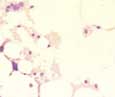

Im peripheren Blutbild sind alle drei Zellreihen deutlich vermindert oder ganz fehlend. Die Erythrozyten sind oft ausgeprägt makrozytär, können aber auch normozytär sein. Die Retikulozyten

Knochenmark:

Das Knochenmark ist hypozellulär oder aplastisch. Im Knochenmarkaspirat imponieren leere Brökel mit einem Netz aus Retikulumzellen (Fibroblasten) ohne hämatopoietische Elemente. Die wenigen noch vorhandenene Zellen sind Makrophagen, Mastzellen, Lymphozyten und Plasmazellen. Während nach Zytostatikatherapie auch die Lymphozyten weitgehend fehlend, sind diese bei der aplastischen Anämie als Ausdruck des Autoimmungeschehens meist relativ vermehrt. In diesem Fall ist vor allem bei schlecht ausgestrichenen Knochenmarkbrökeln die Abgrenzung von einer lymphoproliferativen Neoplasie nicht einfach, weshalb immer auch die Immunphänotypisierung (Biopsie, Durchflussszytometrie) beigezogen werden muss. Die Abgrenzung von einem hyopzellulären myelodysplastischen Syndrom ist schwierig. Während milde Reifungsstörungen auch bei verschiedenen Knochenmarkaplasien im Sinne von reaktiven Veränderungen vorkommen, sprechen ausgeprägte Dysplasiezeichen für ein myelodysplastischen Syndrom.